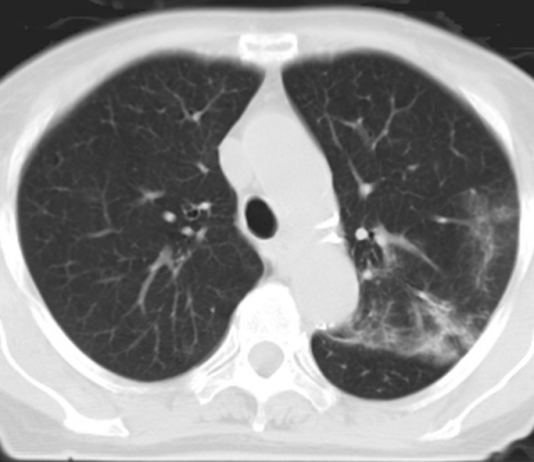

Bimbo di sei anni (due fratelli e genitori asintomatici)

Anamnesi patologica prossima:

Febbre da cinque giorni ,trattata con...